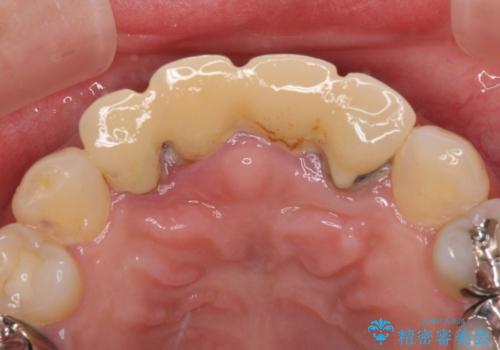

- 地元の歯科医院にて前歯4歯を仮歯に替えたものの、汚れていることが気になるとのことで来院された患者様です。

不適な仮歯の影響で歯肉が腫れていたため、新しい仮歯に替えた後に歯肉の腫れが引くのを待ち、オールセラミッククラウンにて補綴することとしました。

根尖病変が原因で、膿が出てきている歯があったため、仮歯を置き換える際に根管治療を行うこととしました。